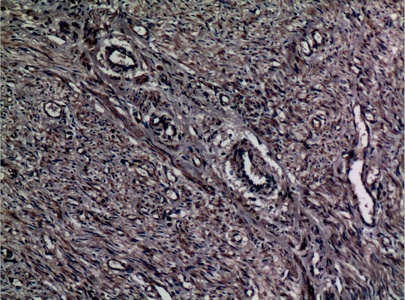

Immunohistochemical analysis of paraffin-embedded human-uterus, antibody was diluted at 1:100